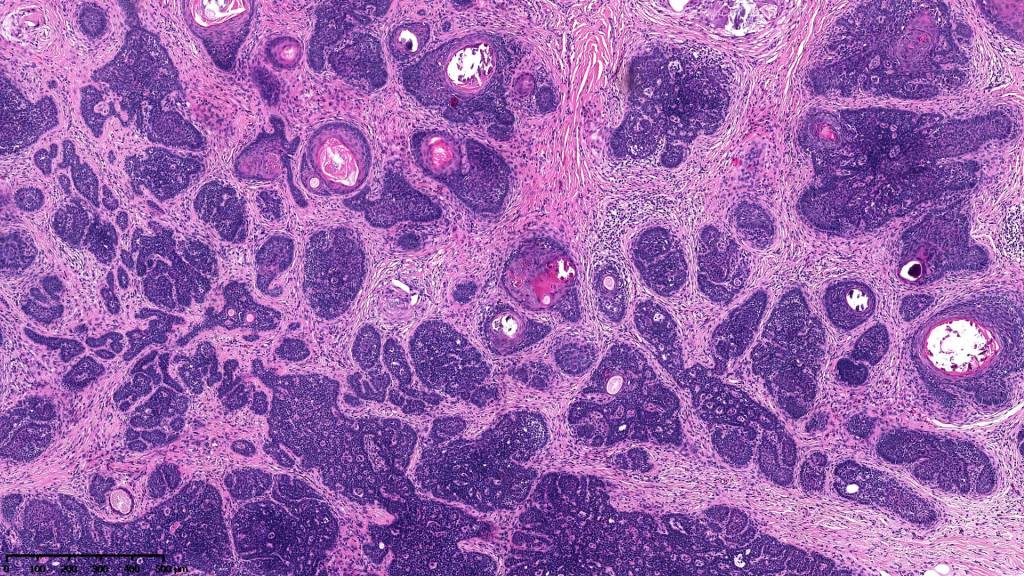

•Variably sized but generally large, basophilic tumor nodules composed of small uniform basaloid cells with minimal cytoplasm

•Peripheral palisading but no retraction artifact or stromal mucin deposition

•Variable keratocysts

•A rich fibromyxoid mesenchymal stroma with variable papillary mesenchymal bodies (sometimes these are absent)

•Trichogerminoma is a distinctive variant being composed of tumor nodules with basaloid cells surrounding pale or eosinophilic micronodules (Zellballen)